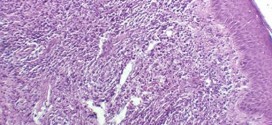

El pseudolinfoma cutáneo. Tumor maligno ó manchas malignas en general y especialmente el formado por células epiteliales o pigmentarias. Los canceres se dividen en dos grandes categorías de carcinoma y sarcoma. La característica básica de la malignidad es una anormalidad de las células, trasmitida a las células hijas, a saber, que se manifiesta por la reducción del control del crecimiento …

La peca melanótica de Hutchinson. Tumor maligno ó manchas malignas en general y especialmente el formado por células epiteliales o pigmentarias. Los canceres se dividen en dos grandes categorías de carcinoma y sarcoma. La característica básica de la malignidad es una anormalidad de las células, trasmitida a las células hijas, a saber, que se manifiesta por la reducción del control …